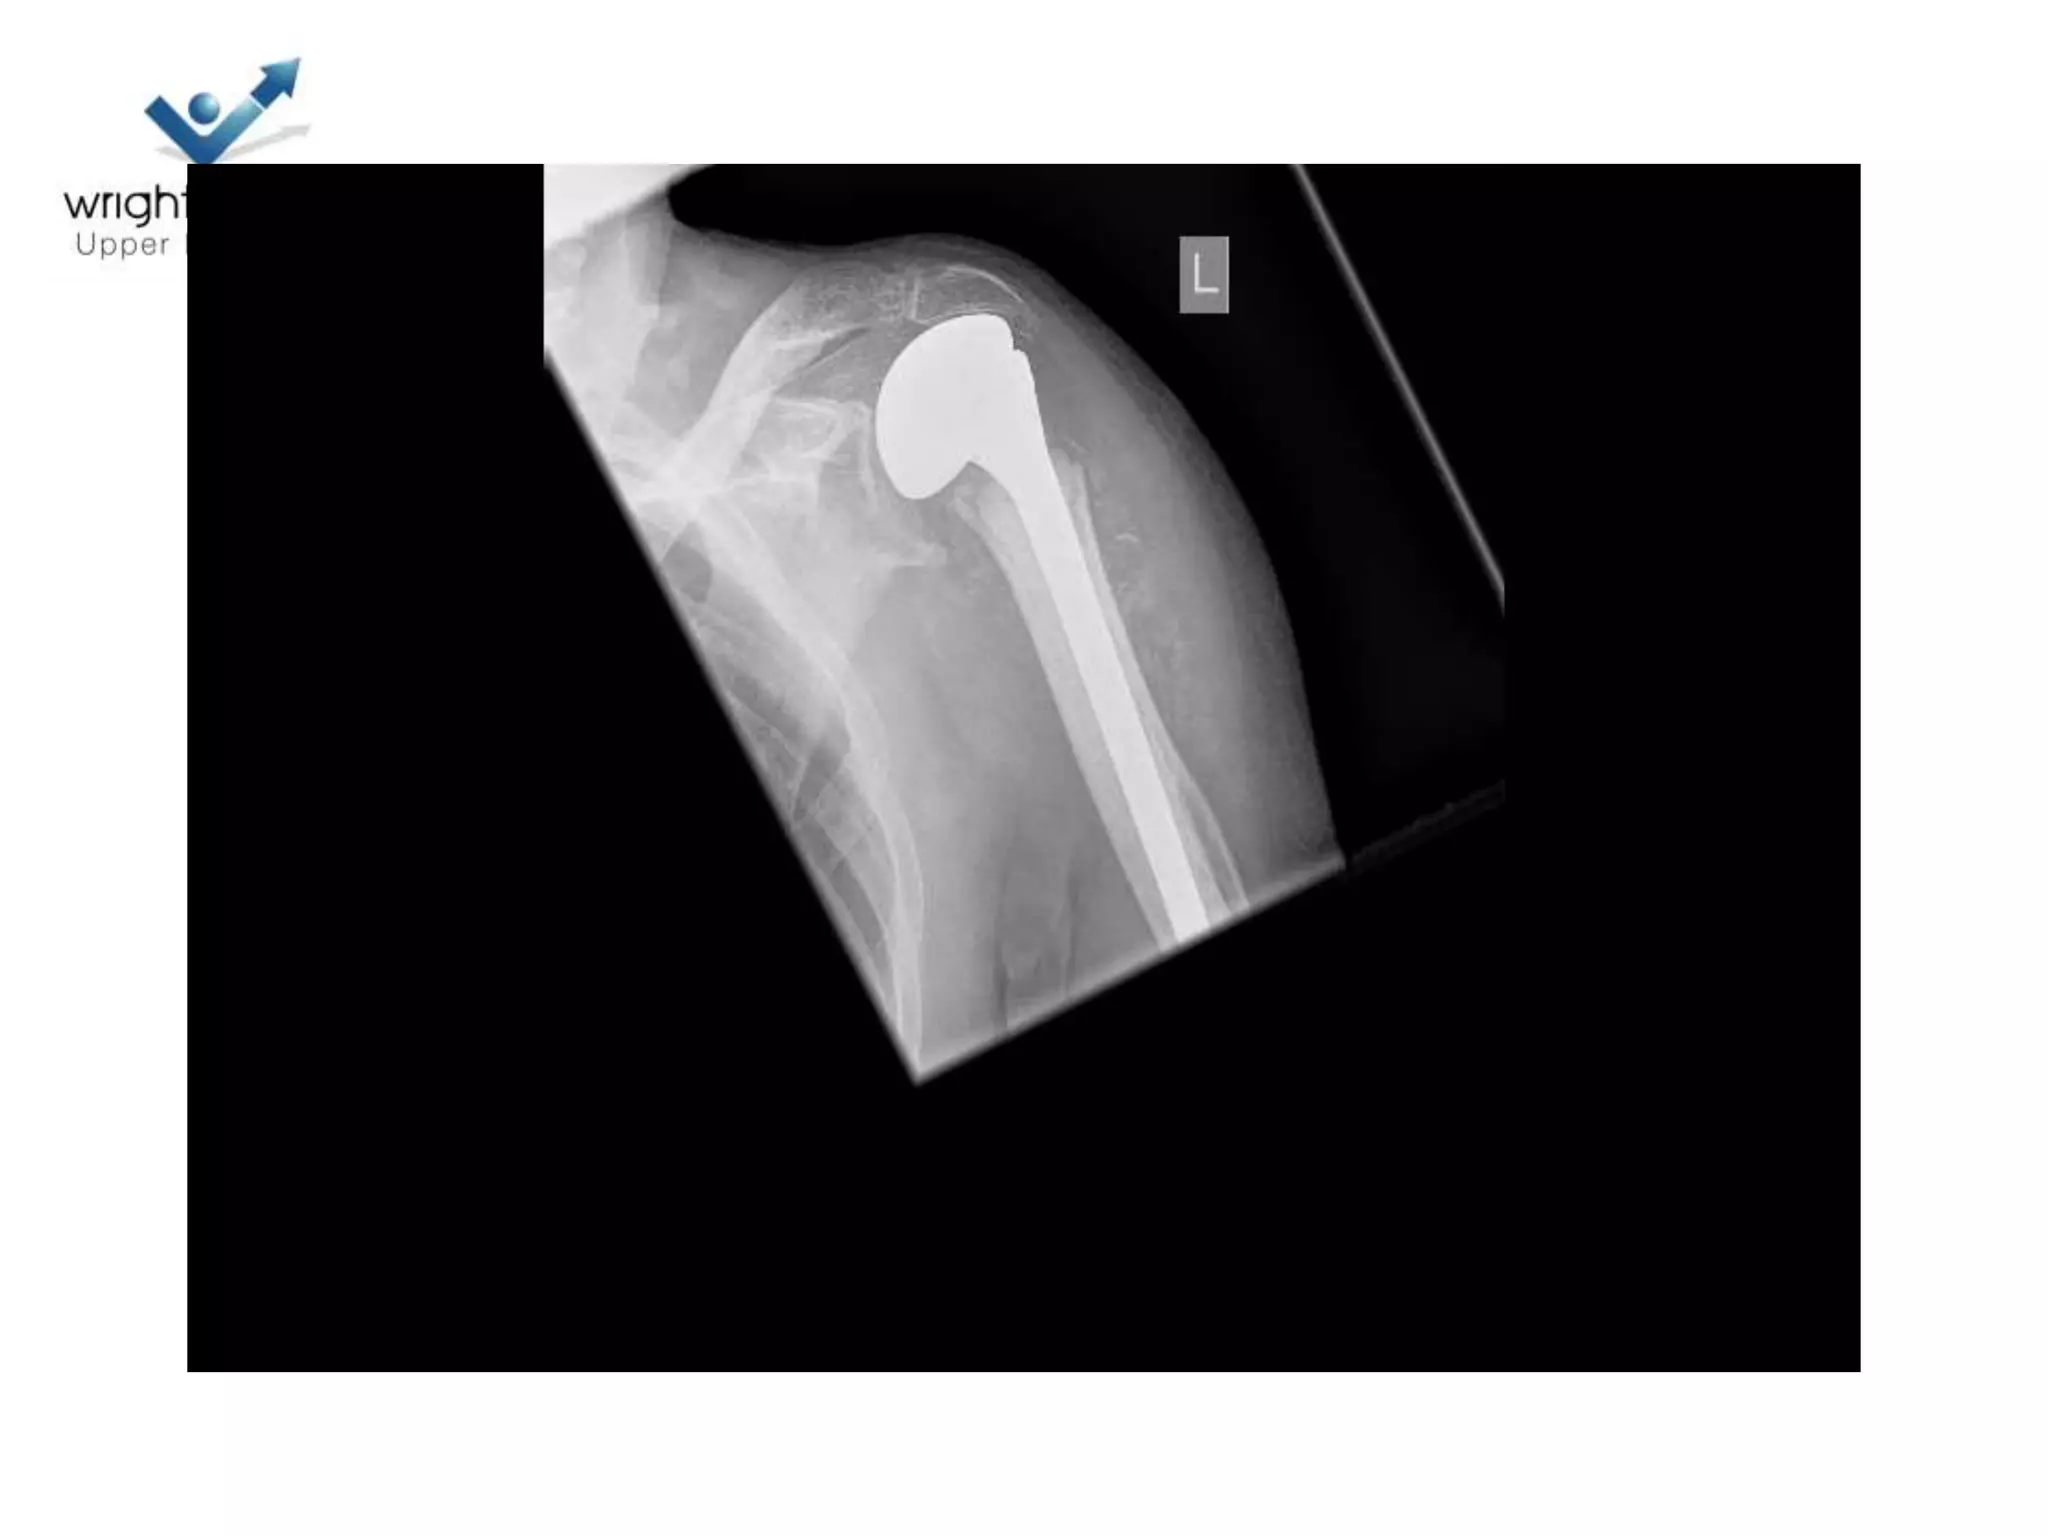

Hemiarthroplasty

• Getting it right

• Depth of prosthesis

• Version of prosthesis

• Size of the head